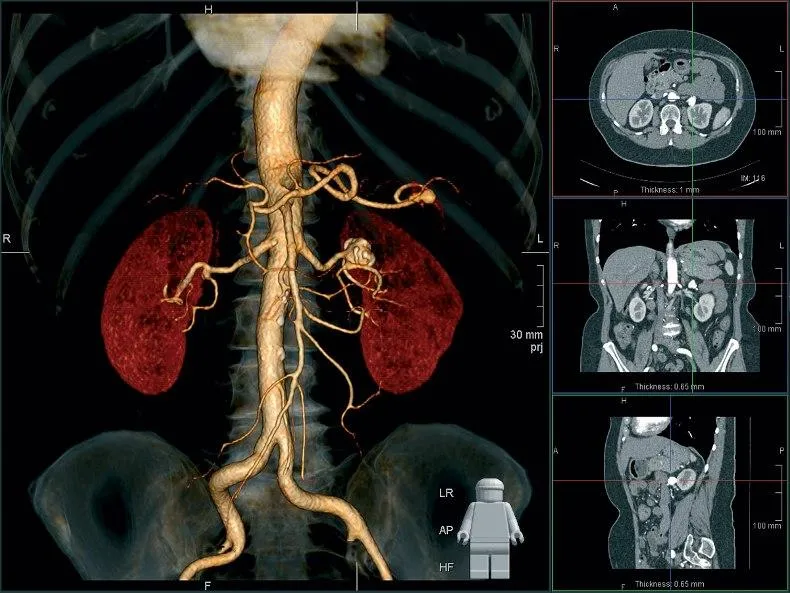

МРТ или УЗДГ сосудов головы используют для получения изображения артерий и вен и поиска патологии, которая привела к неврологическим симптомам. Методы имеют ключевую разницу в принципе работы.

Ультразвуковая допплерография сосудов головы и шеи – это вид УЗИ, определяющий состояние кровотока обсуждаемой области. Метод является безопасным, успешно показывает изменения артерий и вен, наличие турбулентного тока, скорость движения плазмы и форменных элементов внутри них. Ультразвук, проходя через ткани с разной плотностью, отражается обратно к датчику. Компьютер обрабатывает сигнал, а доктор видит на экране монитора изображение. Цвет сосуда зависит от направления движения крови: к датчику – красный, в другую сторону – синий.

Магнитно-резонансная томография – высокотехнологичный и безопасный метод диагностики. МРТ головного мозга позволяет определить причину неврологической патологии, в том числе сосудистого происхождения при выполнении МР-ангиографии. В основе метода лежит использование магнитного поля. Последнее возбуждает протоны водорода, которых больше всего в насыщенных водой тканях. Обратный сигнал улавливается датчиками, программа обрабатывает показатели, а врач получает изображение.

Шаг снимков начинается от 1 мм. Тонкие срезы позволяют сделать результат достоверным и информативным. При изучении мозга могут применять МР-ангиографию с контрастом. Проведение усиленного сканирования сосудов даст информацию о наличии:

- стеноза;

- васкулита;

- аневризмы и расслоения артериальной стенки;

- артериовенозной мальформации и др.